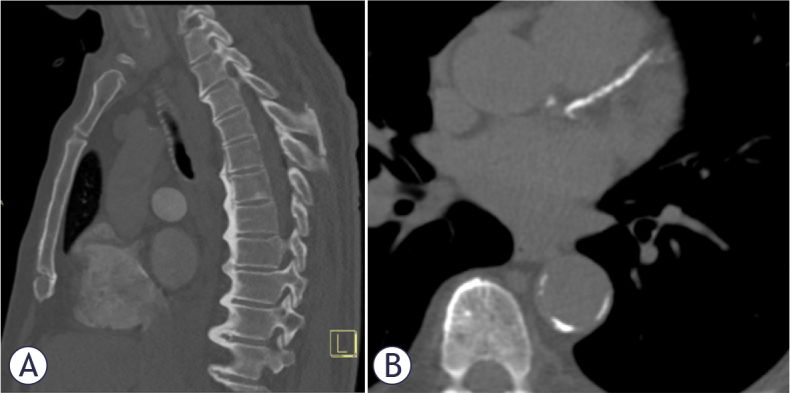

Patients and methods: The research comprised patients referred for CCTA due to a clinical suspicion of coronary artery disease. DISH, CAC score and EAT attenuation were quantified using non-contrast imaging. Diagnosis of DISH was based on Resnick criteria. The CCTA was assessed for the presence of obstructive coronary artery disease (CAD). The association between DISH and the extent of CAC was explored, using correlation analysis and multivariate regression.

Results: The study cohort included 219 participants. The prevalence of DISH was 7.8%. In univariate logistic regression, body mass index (BMI) (odds ratio [OR] 1.133, p = 0,005), age (OR 1.055, p = 0,032) and diabetes (OR 3.840, p = 0,015) were significantly associated with the condition. However, this association did not persist on multinomial multivariate analysis, but gender, age, hypertension and EAT attenuation were found to be significantly associated with the increasing CAC strata.